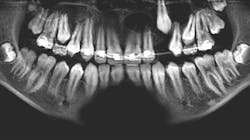

A 14-year-old female presented to her general dentist complaining of pain in the right posterior mandible and mobility of tooth no. 31. Her medical history was otherwise unremarkable. A panoramic radiograph revealed a large, multilocular radiolucent lesion within the entire ramus and posterior body of the right mandible. Tooth no. 32 was within the lesion. Cortical expansion in the area of the lesion was notable. All adjacent teeth were vital. A panoramic radiograph taken at the completion of orthodontic treatment 18 months previously showed no evidence of the lesion.